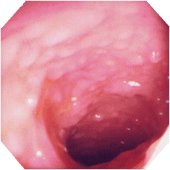

| ■診断基準 次のa)のほか、b)のうちの1項目、およびc)を満たし、下記の疾患が除外できれば、確診とする。 a)臨床症状:持続性または反復性の粘血・血便、あるいはその既往がある。 b)@内視鏡検査:i)粘膜はびまん性におかされ、血管透見像は消失し、粗像または細顆粒状を呈する。さらに、もろくて易出血性(接触出血)を伴い、粘血膿性の分泌物が付着しているか、ii)多発性のびらん、潰瘍、iii)偽ポリポーシスを認める。 A注腸X線検査:i)粗ぞうまたは細顆粒状の粘膜表面のびまん性変化、ii)多発性のびらん、潰瘍、iii)偽ポリポーシスを認める。その他、ハウストラの消失(鉛管像)や腸管の狭小・短縮が認められる。 c)生検組織学的検査:活動期では粘膜全層にびまん性炎症細胞浸潤、陰窩膿瘍、高度な杯細胞減少が認められる。緩解期では腺の配列異常(蛇行・分岐)、萎縮が残存する。 上記変化は通常直腸から連続性に口側にみられる。 b)c)の検査が不十分、あるいは施工できなくとも、切除手術または剖検により、肉眼的および組織学的に本症に特徴的な所見を認める場合は、下記の疾患が除外できれば、確診とする。 除外すべき疾患は、細菌性赤痢、アメーバ赤痢、サルモネラ腸炎、キャンピロバクタ腸炎、大腸結核などの感染性腸炎が主体で、その他にクローン病、放射線照射性大腸炎、薬剤性大腸炎、リンパ濾胞増殖症、虚血性大腸炎、腸型ベーチェットなどがある。 注1)まれに血便に気付いていない場合や、血便に気付いてすぐ来院する(病悩期間が短い)場合もあるので注意を要する。 注2)所見が軽度で診断が確実でないものは「疑診」として取り扱い、後日再燃時などに明確な所見が得られた時に本症と「確診」する。 棟方昭博:厚生省特定疾患難治性炎症性腸管障害調査研究班 平成9年度研究報告書

■活動期内視鏡的所見による分類

注12)内視鏡的に観察した範囲で最も所見の強いところで診断しする。 内視鏡検査は前処置なしで短時間で施行し、必ずしも全大腸を観察する必要はない。 棟方昭博:厚生省特定疾患難治性炎症性腸管障害調査研究班 平成9年度研究報告書